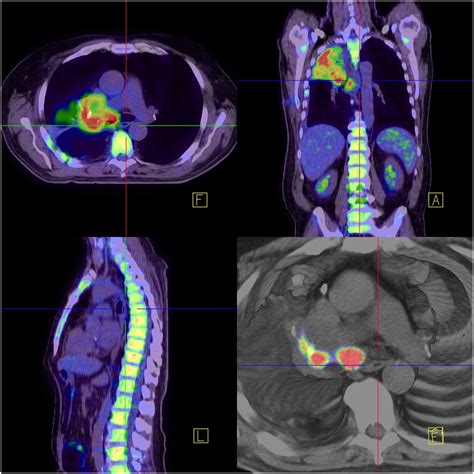

PET-CT scans are a powerful diagnostic tool that combines the strengths of both PET and CT scans. PET scans use a radioactive tracer to highlight areas of high metabolic activity, which is often indicative of cancer cells. CT scans, on the other hand, provide detailed anatomical images of the body. When combined, PET-CT scans offer a comprehensive view of both the structure and function of the body's tissues, making them invaluable in the diagnosis and staging of Pet Ct Lung Cancer.

PET-CT scans involve the injection of a radioactive tracer, typically a form of glucose, into the patient's bloodstream. Cancer cells, which have a higher metabolic rate, absorb more of the tracer than normal cells. The PET scanner then detects the radiation emitted by the tracer, creating images that highlight areas of high metabolic activity. Simultaneously, the CT scanner takes detailed images of the body's structures, which are then fused with the PET images to provide a precise location of the cancerous cells.

Interpreting the results of a PET-CT scan involves a detailed analysis by a radiologist. The images are reviewed to identify areas of high metabolic activity, which may indicate the presence of cancer. The results are then shared with the patient's healthcare team, who will discuss the findings and develop a treatment plan. It is important to note that while PET-CT scans are highly accurate, they are not foolproof. False positives and false negatives can occur, and additional tests may be needed to confirm the diagnosis.